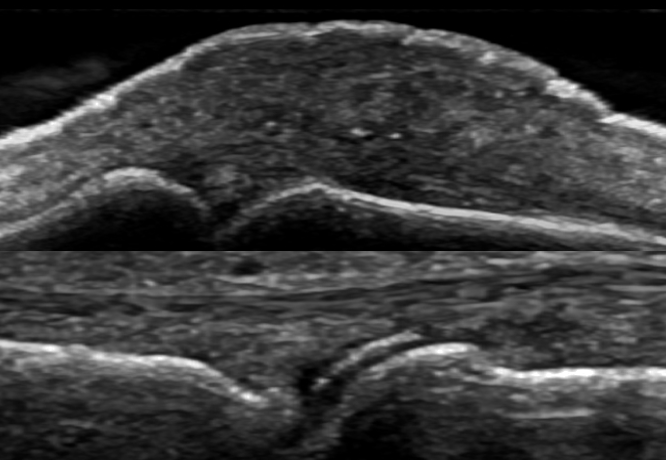

Consente di effettuare visite più scrupolose, permettendo spsesso di aver un quadro chiaro fin dalla prima valutazione.

Consente inoltre al paziente di vedere con i propri occhi il problema da risolvere, ed capire quindi il motivo del trattamento consigliato

Ecografia articolare